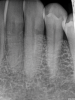

(5.) Close-up clinical and radiographic views of an ECR lesion presenting as a pink spot on the cervical aspect of tooth No. 7.

Figure 5

(6.) Close-up clinical and radiographic views of an ECR lesion presenting as a pink spot on the cervical aspect of tooth No. 7.

Figure 6

When using periapical radiographs in diagnosis, external resorptive defects should appear to move when captured from differing angulations and will have a visible and intact pulp chamber in all but advanced cases.1 All radiographic findings can help to differentiate ECR lesions from internal root resorption lesions, which have symmetrical, smooth, and clearly defined walls that appear to balloon out from the pulp chamber and do not appear to move with multiple parallax images. Conversely, ECR lesions have a less defined, irregular, and "ragged" or "moth-eaten" appearance and demonstrate variations in density, which makes them distinct from internal root resorption lesions that are usually uniform in density (Figure 7).2,14

On radiographs, early ECR lesions may exhibit a diminutive spot at the cementoenamel junction (CEJ), which may be confused with cervical burnout, but throughout the majority of the lesion, the root canal should be visible and intact. Advanced ECR lesions will appear as large radiolucent areas with less well-defined or "moth-eaten" borders that can extend into the pulp space.25 If an ECR lesion is in the repair-remodeling stage of development, it may appear more radiopaque due to the ossification of granulation tissue. Radiopaque spots may also be observed due to disruption of the PRRS that has led to local calcification of pulp tissue.6